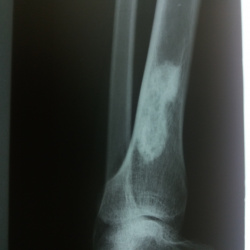

Мужчина 1963 г р . отправлен терапевтом, в направление артроз под вопросом. Подскажите пожалуйста, что за участок десьрукции в метаэпифизе?